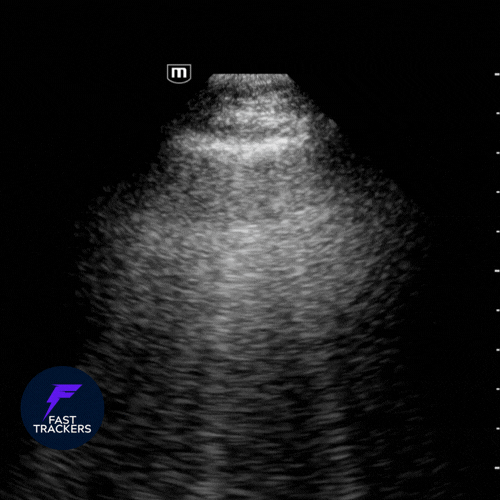

🌪️ Pneumothorax

L’air sépare la plèvre viscérale de la pariétale.

- Absence de glissement pleural : ligne pleurale statique.

- Absence de lignes B, lignes A prédominantes.

- Mode M : « signe du code barre » (lignes horizontales parallèles au-dessus et au-dessous de la plèvre, sans granulation).

- Point poumon : zone de transition entre glissement présent et absent → signe spécifique de pneumothorax.

Explorer en priorité les régions antérieures et supérieures, car l’air remonte → Chez un patient allongé, commencer par les zones antérieures.